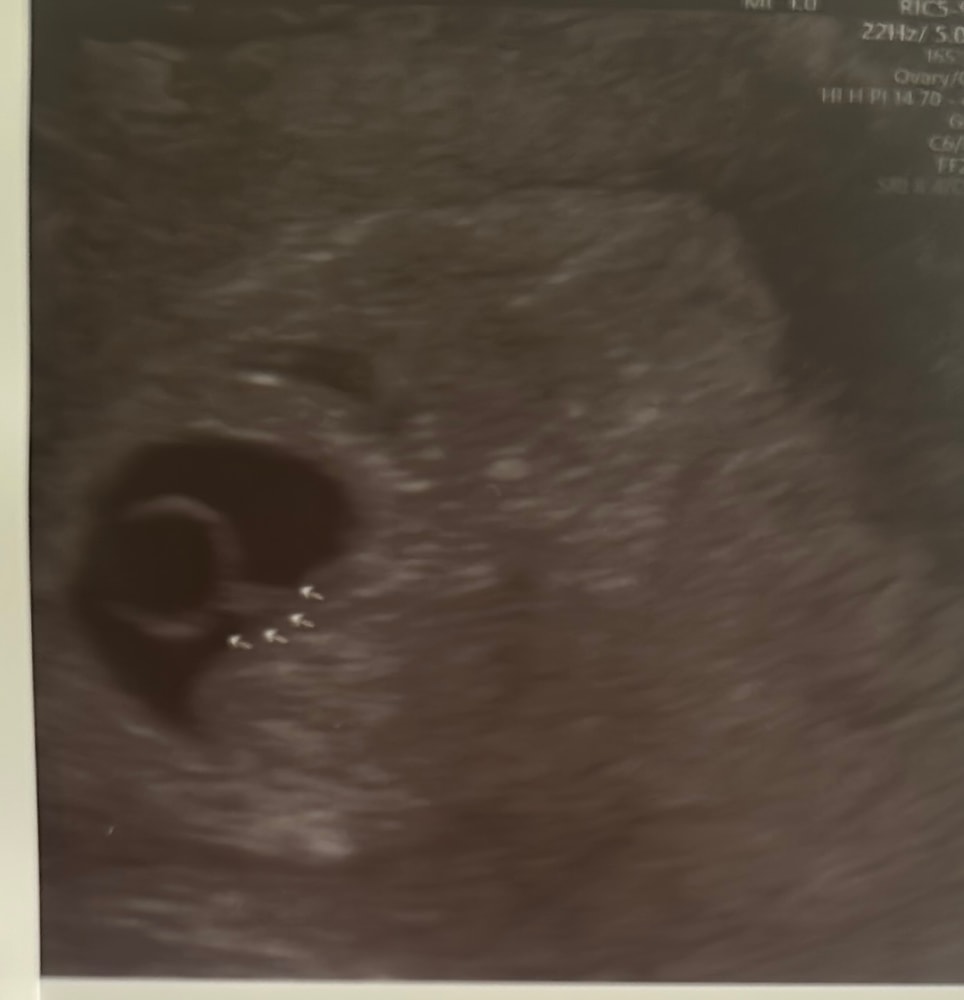

Результаты УЗИПри ктр эмбриона 2 мм, сб еще не было . У меня 19 дпп это норма ?

Какой хорошенький, какой ровненький! Все у вас в порядке. Сегодня так же была на узи. Ре сказала, что услышать сб можно после 25 дпп, если до - то скорее это исключение из правил. Сходите через 1,5 - 2 недели, будет сб💖

На 20 дпп был жм и плодное яйцо, на 22 дпп уже эмбриончик с пульсацией ктр 1,5 мм. Подождите еще) рановато☺️

На 19 дпп даже не пытались слушать сб, эмбрион еле еле визуализировался.

На 33 дпп около кто 3 см и уже было сб.

На 23 дпп хгч был 21600, пя 14, жм 3

На 30 дпп пя 25, жм 5, ктр 8, сердцебиение

У меня на 26 дпп ещё было пониженное сб, врач сказал, только недавно появилось. На 19 дпп и эмбрион ещё не у всех находят.